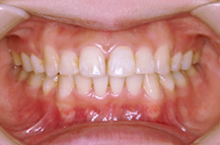

歯並びの幅が広がって、きれいなU字型になってきました。これが本来の歯列の形です。

引っ込んでいた下顎が自然に前に出て、きれいな横顔になりました。

口角がきれいに広がる素敵な笑顔になりました。